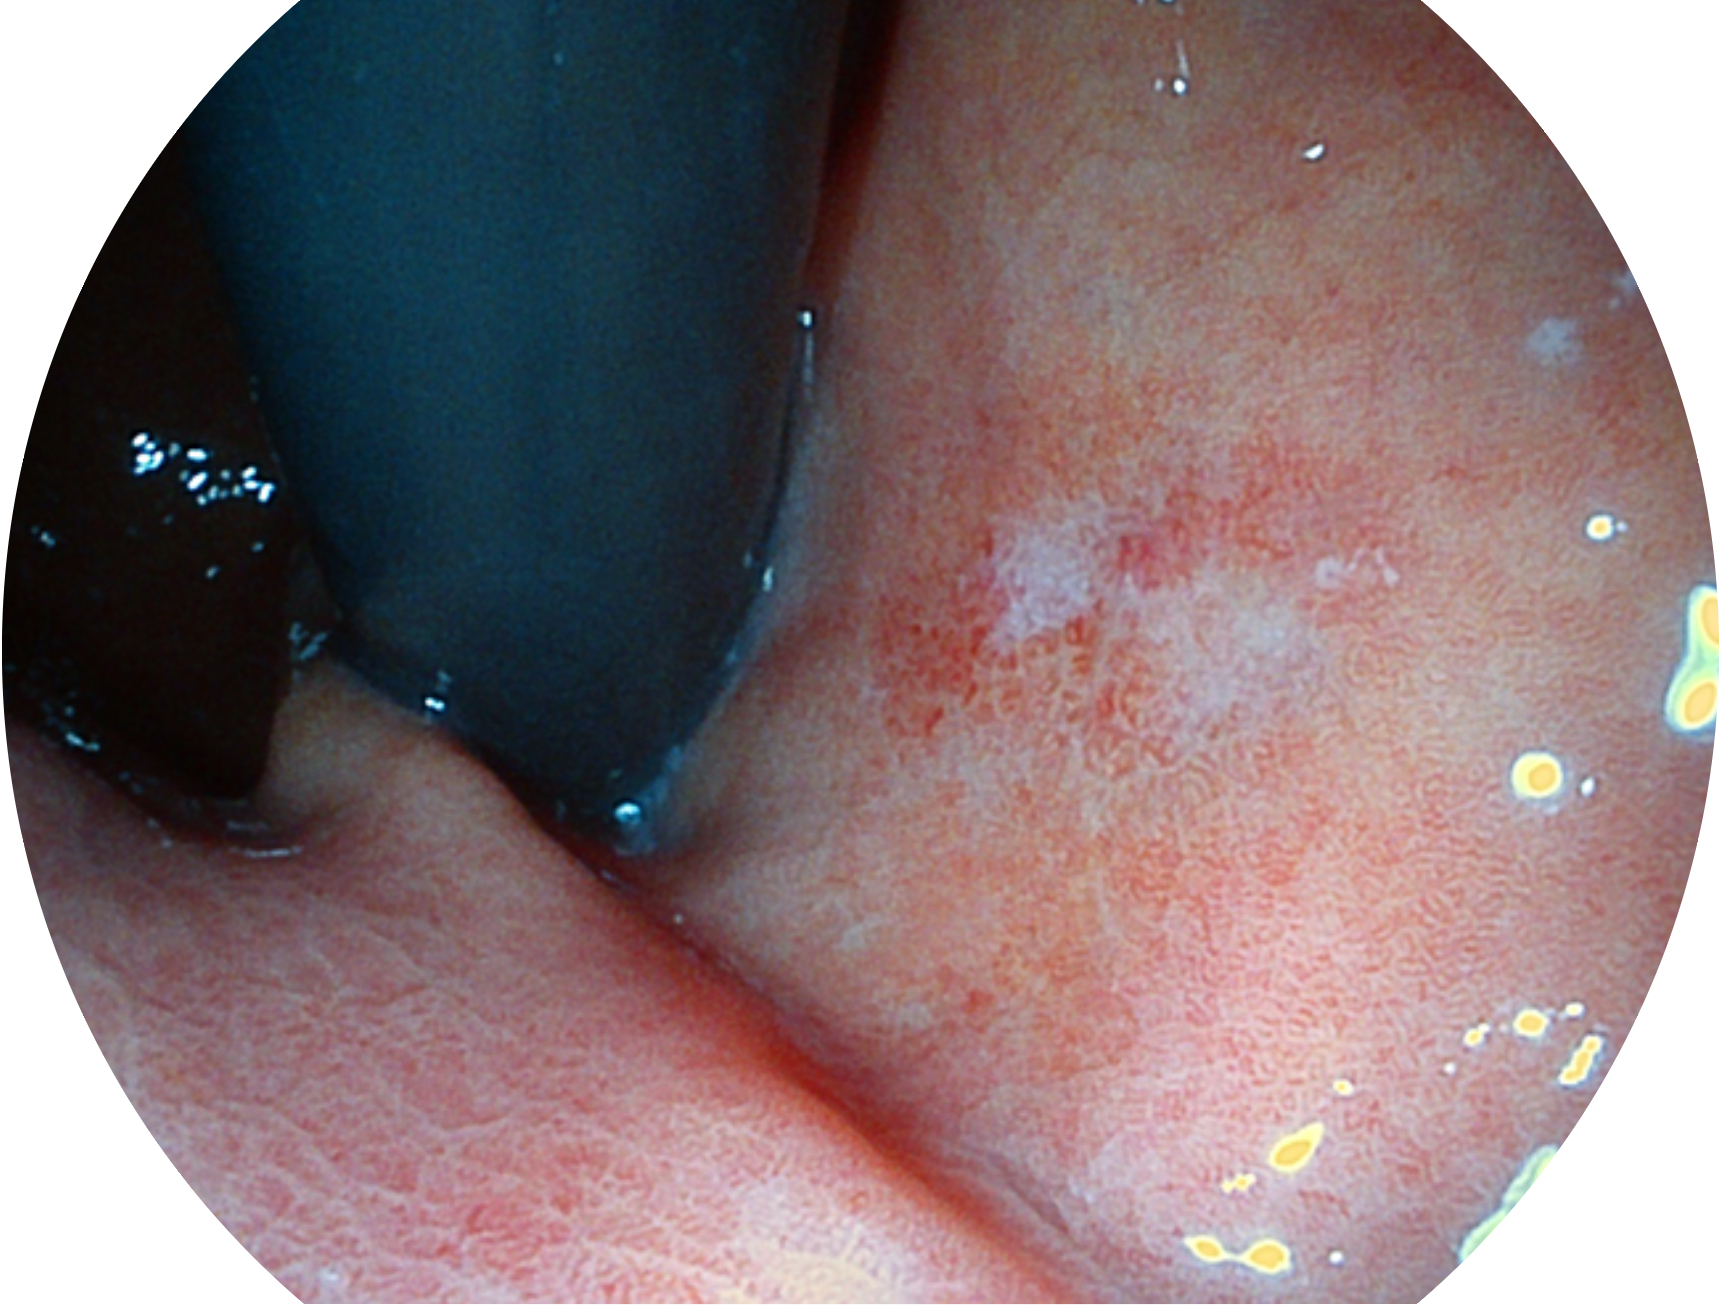

开立新开发的内镜染色技术,主要是基于多波长LED 光源的开发,VLS-55Q 四波长LED 光源是由四个不同颜色的LED光按照相应照明模式所规定的特定发光比例进行合束后形成,合束后形成的照明光的光谱由红光、绿光、蓝光及蓝紫光这四个不同的波段范围构成。具有更高光谱自由度,通过光谱比例的控制,实现了聚谱成像技术,英文全称为“Spectral Focused Imaging, SFI”,缩写为“SFI”和光电复合染色成像技术,英文全称为“Versatile Intelligent Staining Technology, VIST”,缩写为“VIST”。